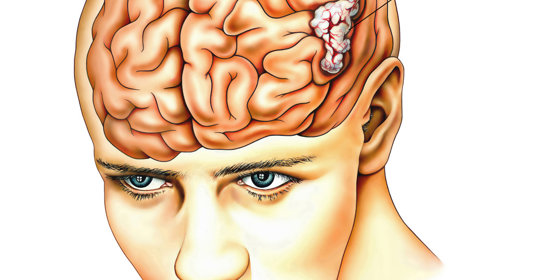

大腦與神經

毛毛樣腦血管病的診斷、治療及預防

短暫性腦缺血發作的診斷與治療方法

創傷性腦損傷的診斷、治療與預防